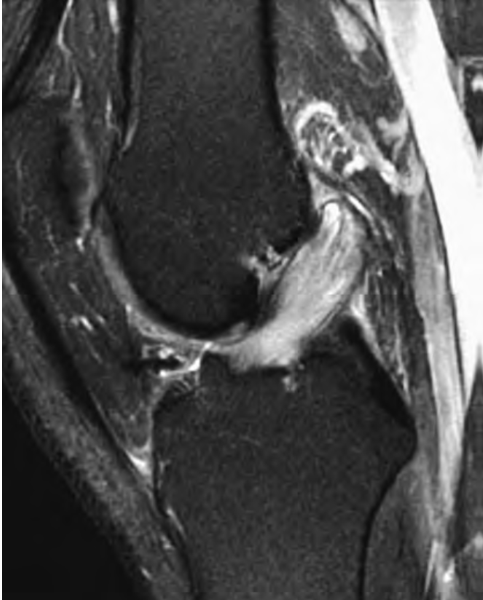

Q. ¿PRINCIPALES HALLAZGOS DE ESTAS IMÁGENES Y A QUE GRADO INESTABILIDAD ROTATORIA POSTEROLATERAL (PLRI) CORRESPONDE ?

Inestabilidad rotatoria posterolateral, grado 1. Resonancia magnética ponderada por PD del FS coronal que muestra una avulsión de la colateral del ligamento cubital lateral proximal y retracción del fragmento óseo (flechas blancas). El edema de la médula ósea se observa en el capitelo (puntas de flecha blancas) y la cabeza radial (asteriscos blancos).